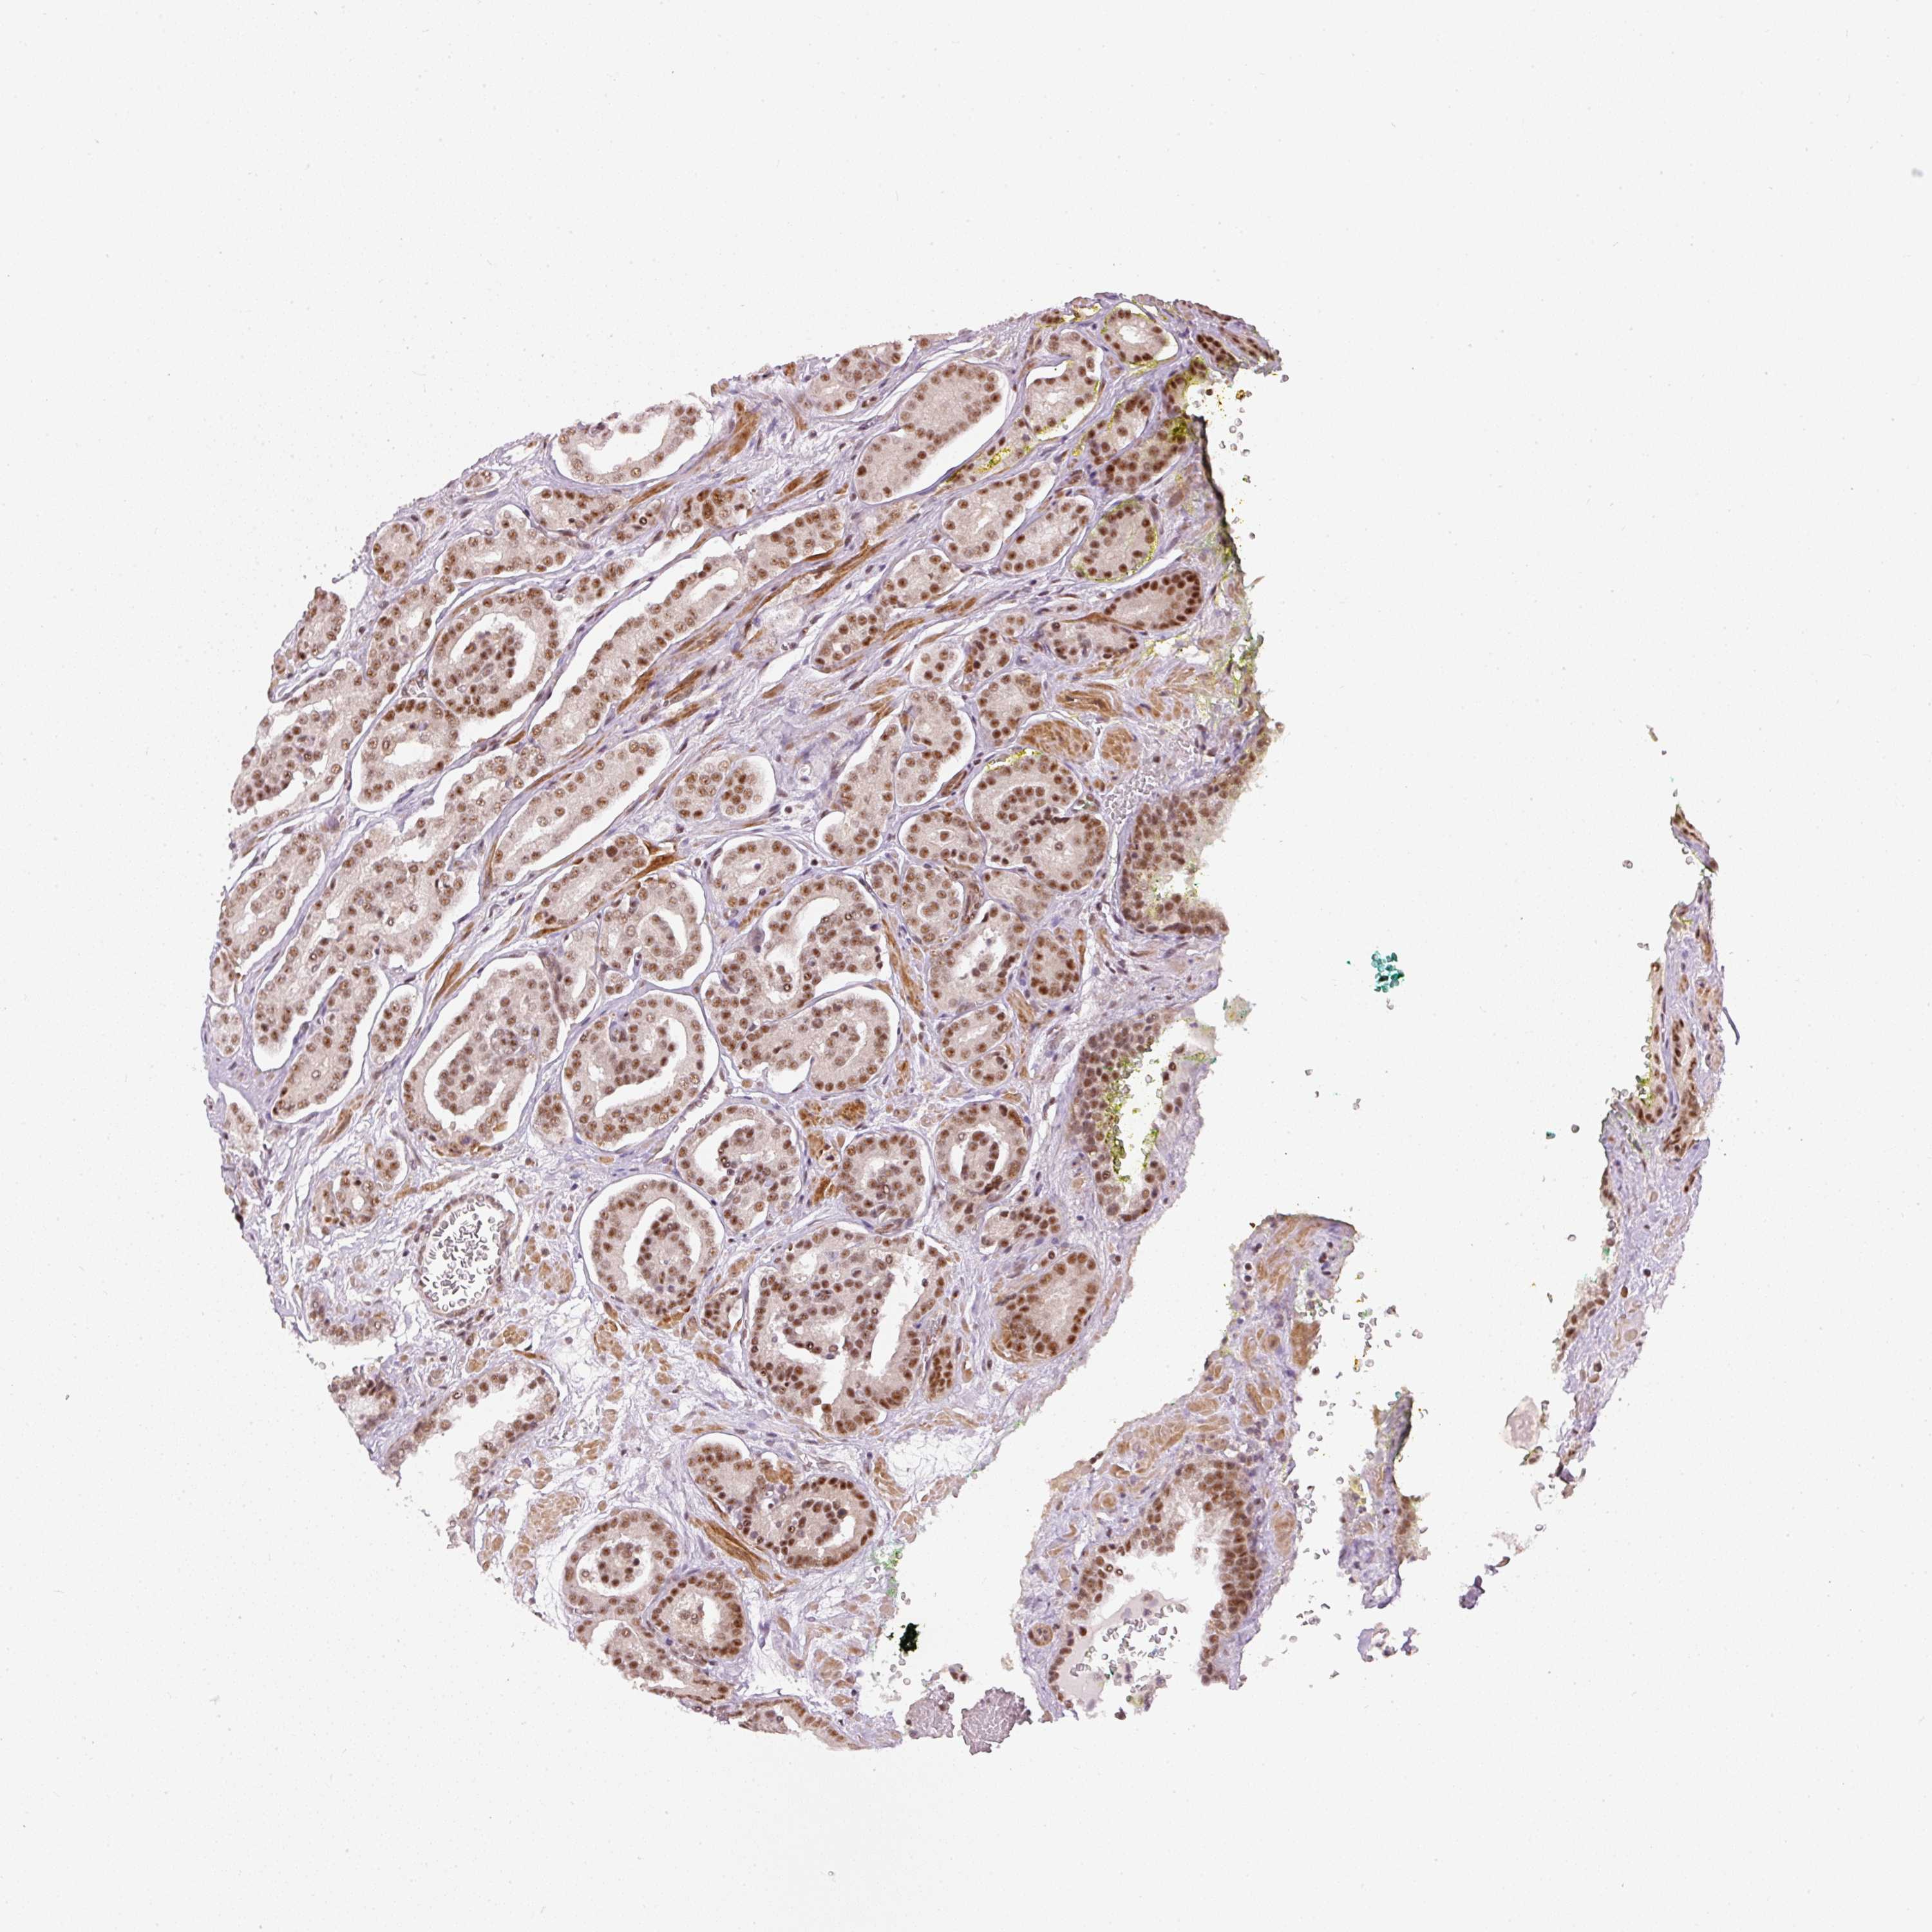

PROSTATE CANCER - Protein expressioni

A mouse-over function shows sample information and annotation data. Click on an image to view it in a full screen mode. Samples can be filtered based on level of antibody staining by selecting one or several of the following categories: high, medium, low and not detected. The assay and annotation is described here.

Note that samples used for immunohistochemistry by the Human Protein Atlas do not correspond to samples in the TCGA dataset.

Antibody stainingi

Antibody staining in the annotated cell types in the current human tissue is reported as not detected, low, medium, or high, based on conventional immunohistochemistry profiling in selected tissues. This score is based on the combination of the staining intensity and fraction of stained cells.

Each image is clickable and will lead to virtual microscopy that enables deeper exploration of all samples and also displays staining intensity scores, fraction scores and subcellular localization as well as patient and tissue information for each sample.

Antibody HPA052953

Staining

High

Medium

Low

Not detected

Intensity

Strong

Moderate

Weak

Negative

Quantity

>75%

75%-25%

<25%

None

Location

Nuclear

Cytoplasmic/membranous

Cytoplasmic/membranous,nuclear

Adenocarcinoma, NOS

Adenocarcinoma, High grade

Adenocarcinoma, Low grade